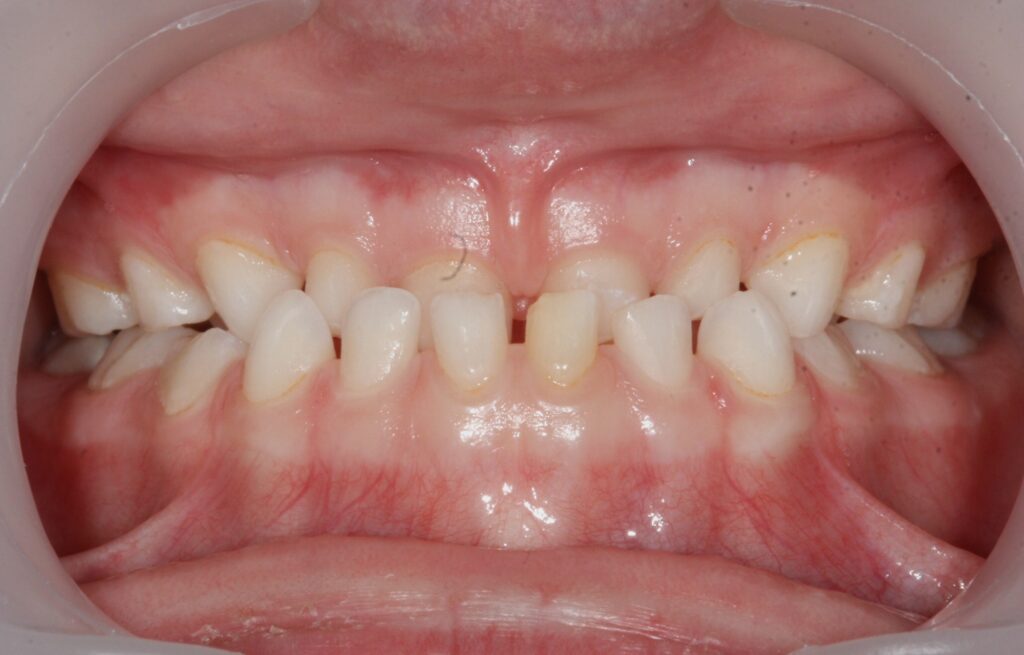

Un cas d’inversion d’articulé latéral:

Un traitement démarré à 6 ans, a permis à cette petite fille de ne pas grandir avec un menton de travers.

Photos à 6, 7 et 10 ans

Un alignement et un ajustage occlusal seront nécessaires lorsque toutes les dents définitives seront présentes.